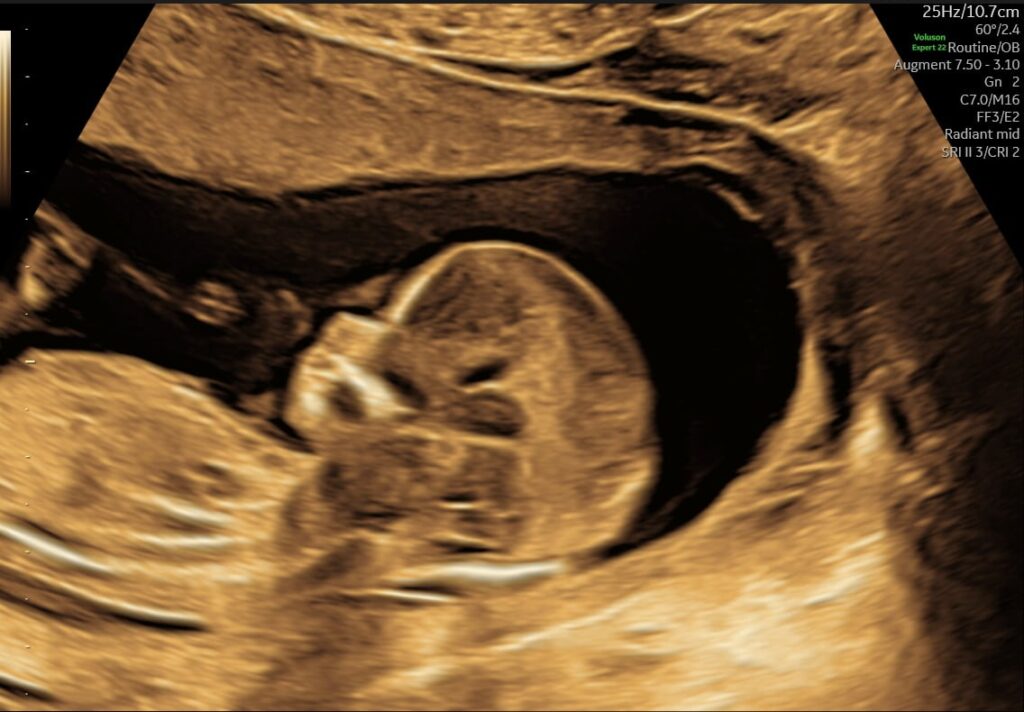

Mange kommende forældre glæder sig til at få at vide, om det er en lille dreng eller pige, der er på vej. Allerede fra uge 14+0 kan vi med en kønsscanning se barnets køn.

Kønsscanning afslører dit barns køn fra uge 14+0 – og du kan supplere med en 3D/4D scanning for at få detaljerede billeder.

Vores jordemoder kan se barnets køn helt fra uge 14 + 0. Hvilket man kan kalde en tidlig kønsscanning, og det giver dig og din partner rig mulighed for at forberede jer på den lille ny.

- Ved en kønsscanning hos praksisjordemoder får du en fin 2D kønsscanning af bedste kvalitet, hvor vi udover at se kønnet ser hjerteblink og lytter til det. Du kan se hvordan den lille ligger og bevæger sig, og det er tydeligt at se hvor hurtigt den lille udvikler sig i maven.

Udover at se kønnet er det bare så dejligt at få et lille ekstra kig ind til den lille på det her tidspunkt i graviditeten, de fleste mærker ikke liv endnu og der er stadig lidt tid til den næste scanning. Er du klar at vide om du skal have en lille dreng eller pige, så book en kønsscanning allerede i dag.